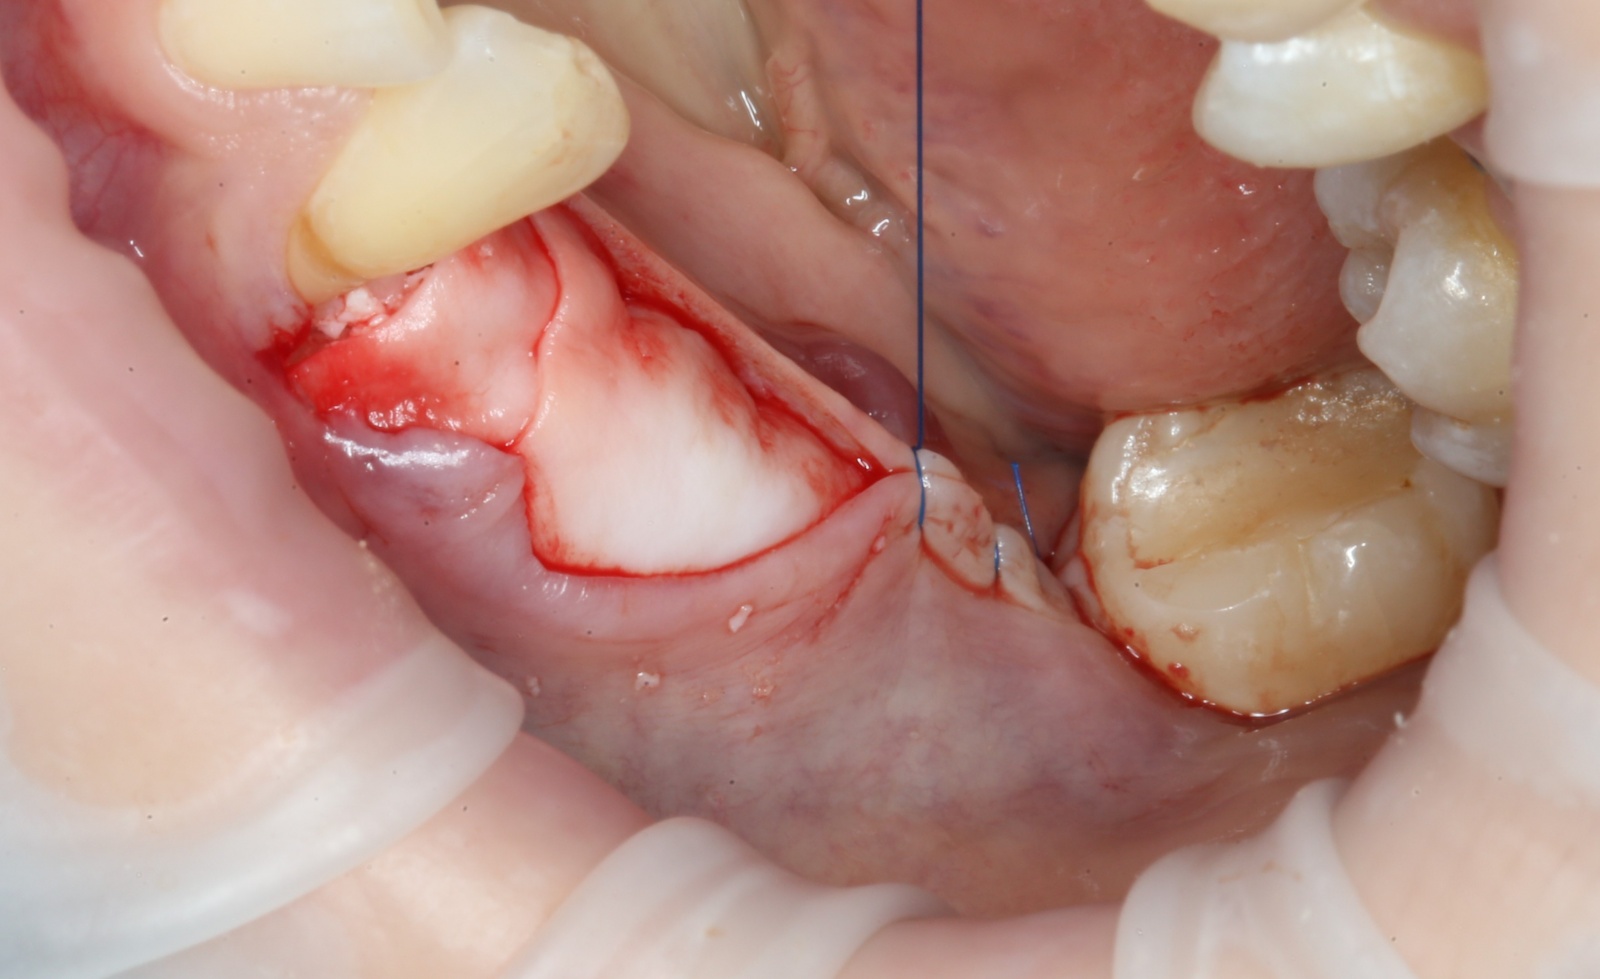

Итак, 5 месяцев позади:

Всё тот же разрез и скелетирование кости:

Фиксирующие винты нам больше не нужны. Неровные костные края сошлифовываются при помощи того же прямого наконечника, но уже с твёрдосплавными шаровидными борами:

Выглядит это так:

Разметка под имплантаты: